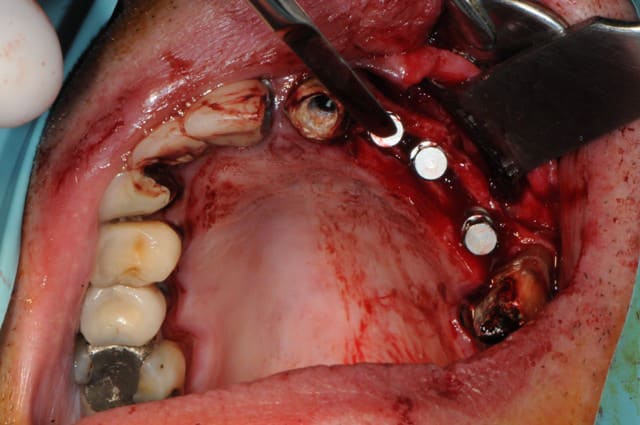

Patiente adressée suite à une ré-hab prothétique fait en 2010, perte de la canine 6 mois après...donc stellite plutôt mobile, comme la 14 et bientôt la 37, mais bon, on commence le projet implanto.

Exo de la 23 + implantation immédiate

Expansion kit Meissegner et lame 15

Pose de 2 implants (13 et 11)

Pose 22 impossible, j'ai tenté, mais crak, bof, j'ai placé en 24 et 25.

Un peu de granules osseuse (23)

Dans l'ordre pour le cas montré pour implants 11 et 13

1-Disque sur la crête

2-Lame 15 impactée (sommet crête et en vestibule (décharges)

3-Ciseaux à os (bone chivel)

4-Forêt 1.2 mm

5-Expanseur rotatif (A-B-C-D-E)

6-Pose implant